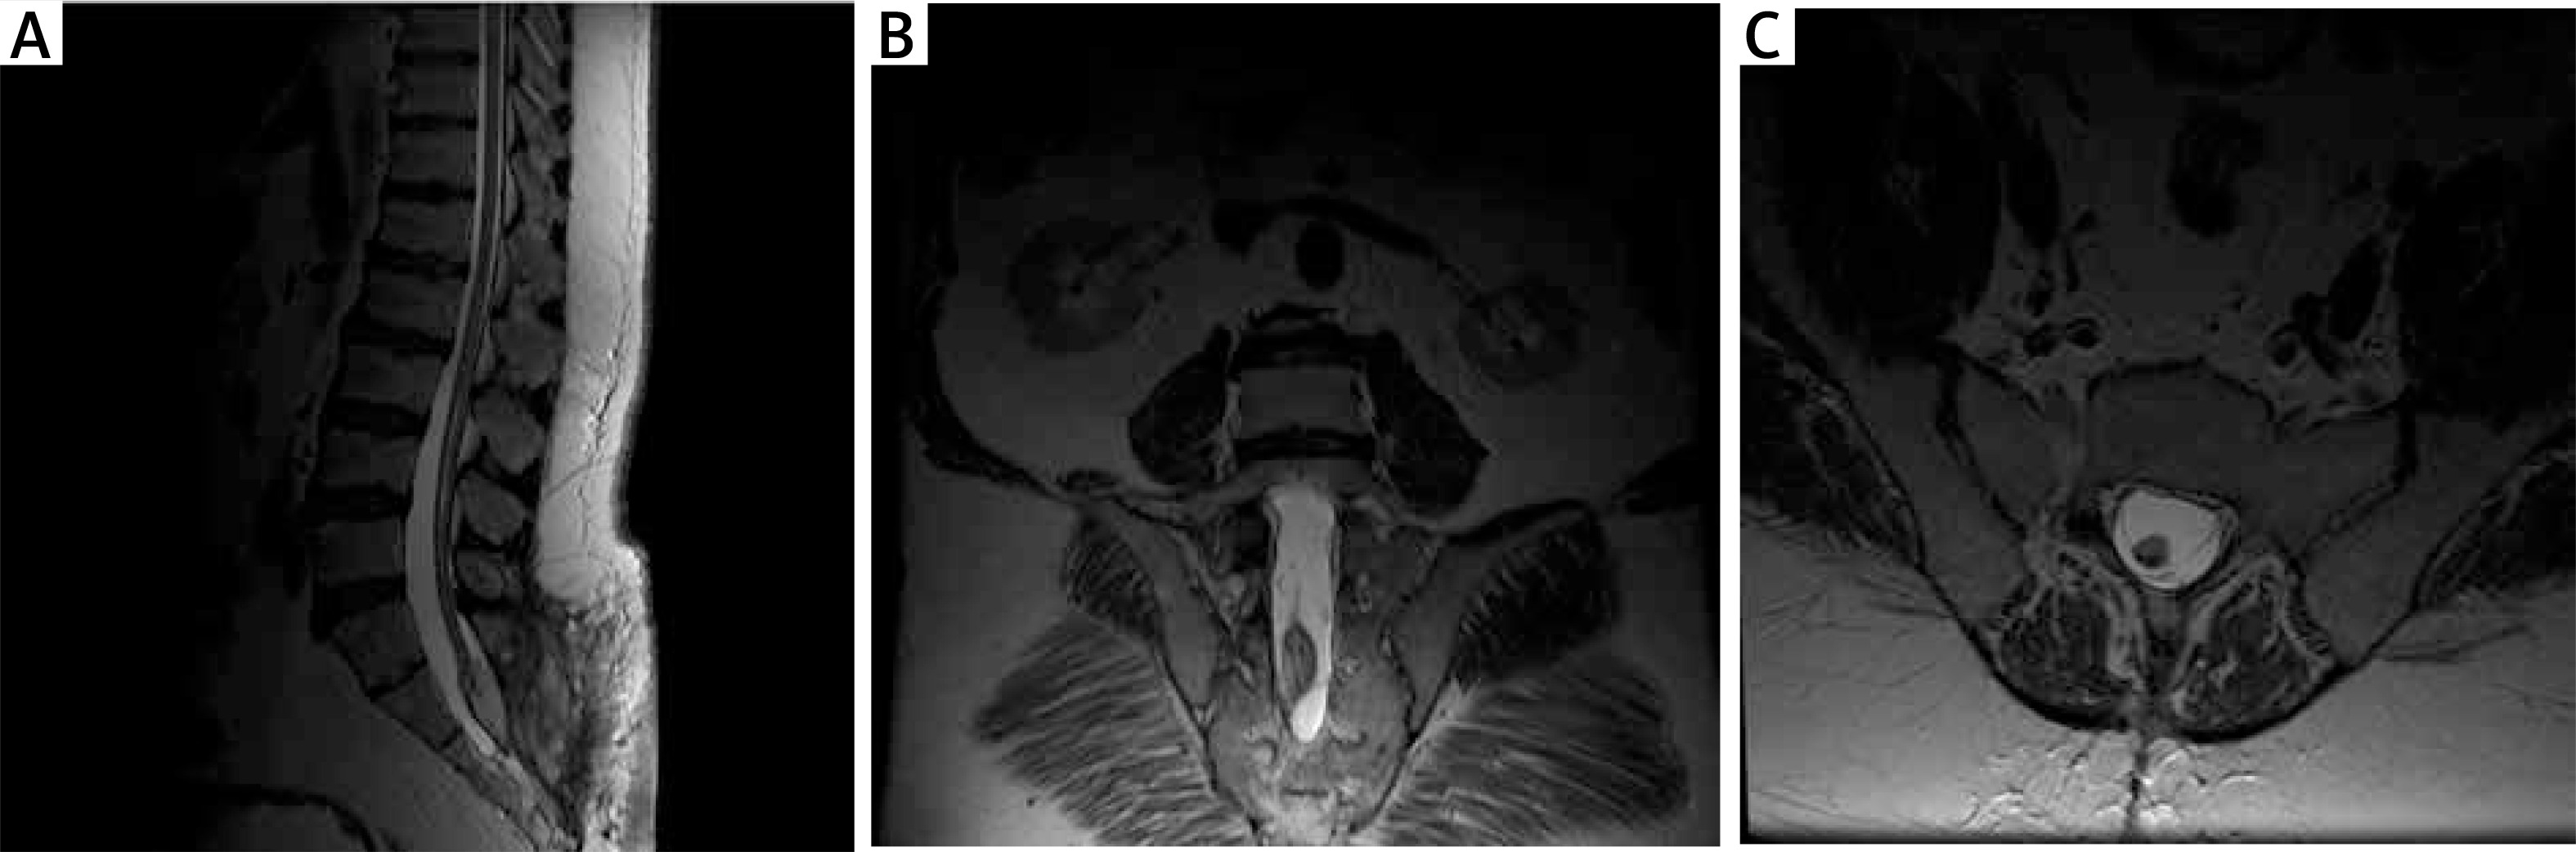

Late postoperative period

Ten months later, during another outpatient visit, MRI was performed (Figure 5). Clinically, the patient’s condition had improved since discharge from the neurosurgery department, pain was significantly reduced, and sphincter function did not deteriorate.

Figure 5

MRI scan at 12 months after surgery in 2 patients. A – MR T2 examination, postoperatively; visible postoperative wound, partially removed lipoma. B – MR T2 examination, postoperative coronal sections; remaining part of the adipoma is visible. C – MR T2 examination, postoperative axial sections